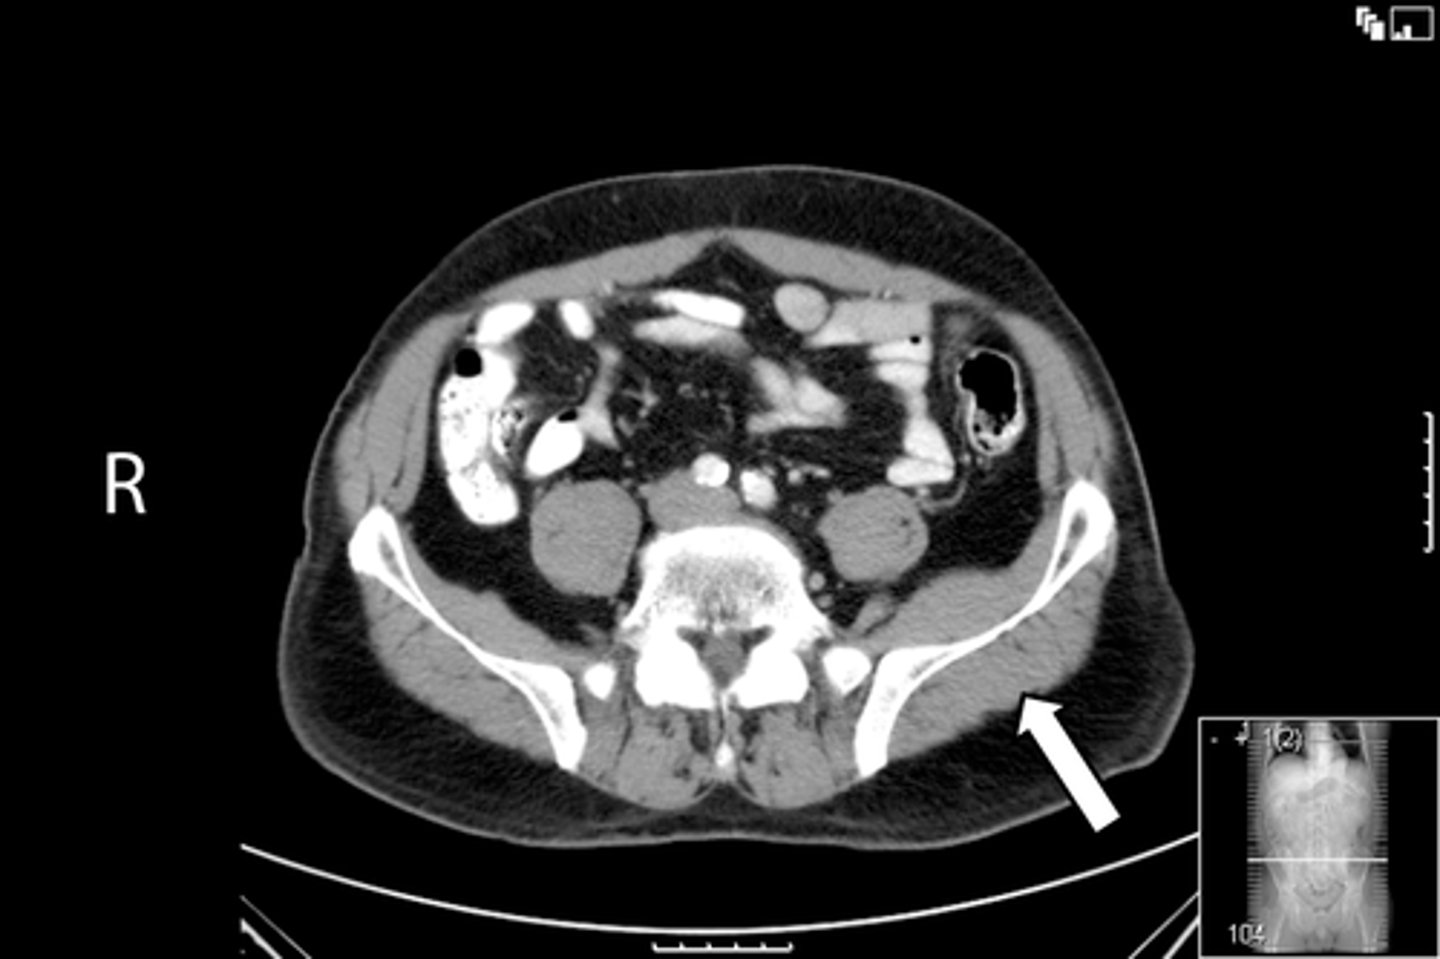

Axial male pelvis CT

What is the image?

55

Aorta

<p>What is indicated in the image?</p>

New cards

What is indicated in the image?

57

IVC

59

L psoas muscle

61

R psoas muscle

63

Terminal ilium